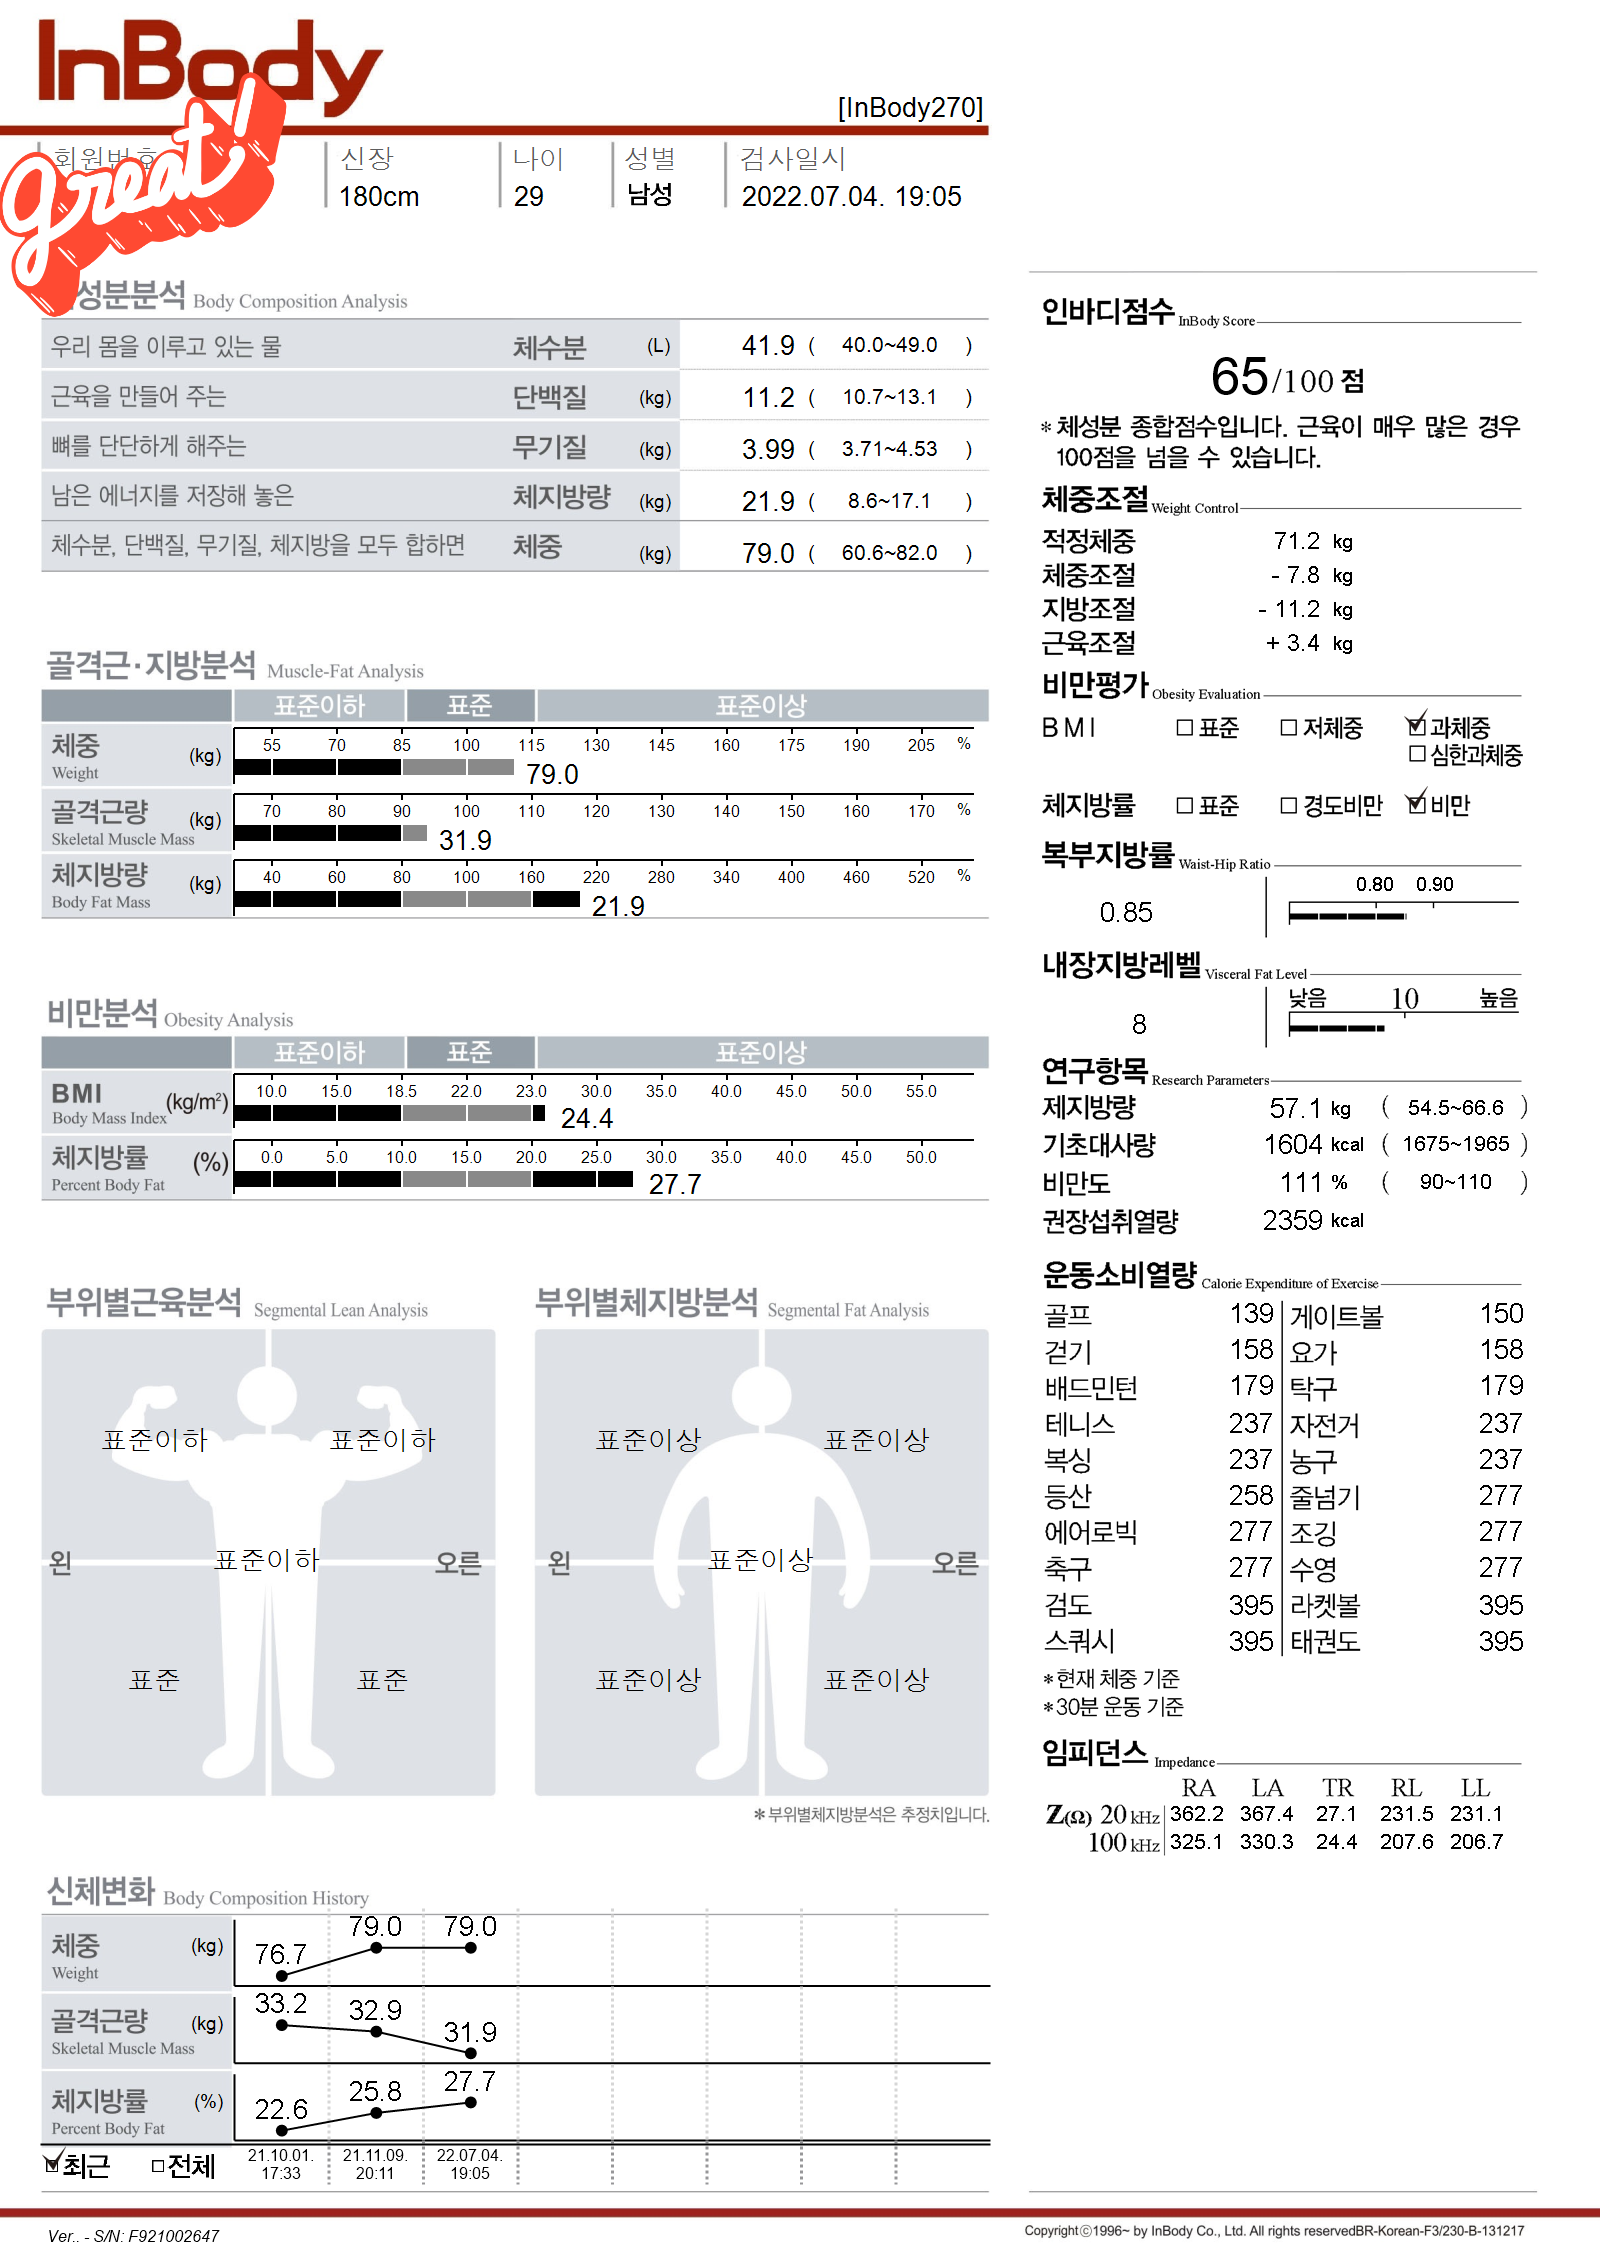

평생 운동이랑은 담 쌓고 살다가 어느날 거울을 봤는데

왠 ET 멸치가 팔다리는 얇은데 뱃살만 나와 있는거보고 기겁함..

30살쯤에 운동을 시작해야겠다고 생각하고 운동 시작...

그래도 몇년전에 비해 뱃살은 많이 줄은 것 같음 ㅋㅋㅋ

어제 인바디 재봤는데 마침 체지방률이 딱 27.7에서 13.8로 절반 되었길래 근황 올려봅니다..